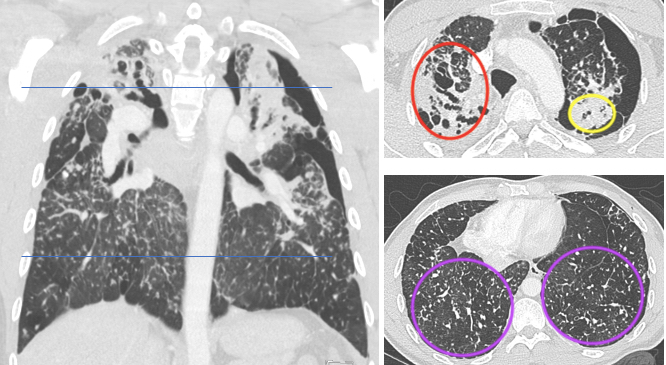

Also, a U.K. team chose the RSNA to present the preliminary findings of the important LungIMPACT study. The aim is to determine if AI helps identify chest x-rays from patients who will benefit most from same-day CT, triaging for an immediate review and report.